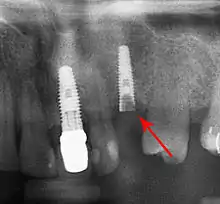

Bone loss (peri-implantitis) on implants over 7 years in a heavy smoker

Fracture of abutment screws (arrow) in 3 implants required removal of the remainder of the screw and replacement.